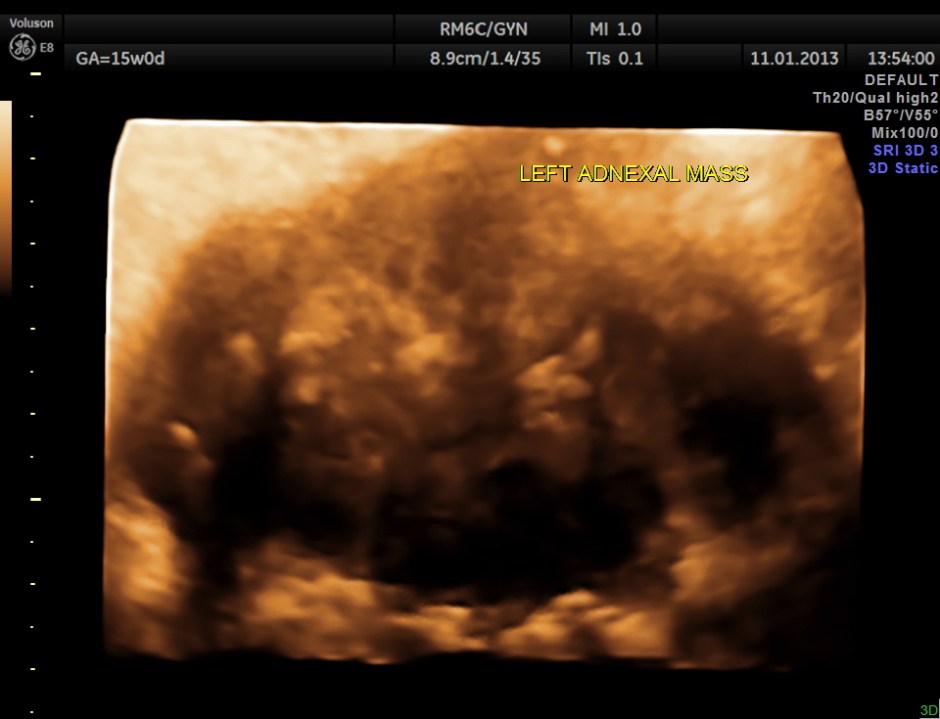

3 D reconstructed image of the left adnexal mass.